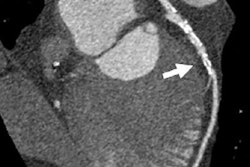

A team led by Dr. Helena Eriksson of Sahlgrenska University Hospital in Gothenburg, Sweden, conducted a study using data from the Swedish CardioPulmonary BioImage Study (SCAPIS), assessing coronary artery calcium scores in 777 men and women taken with CT angiography.

Of the 777 study participants, 20% of the men and 5% of the women had coronary artery calcium scores equal to or higher than 100. The prevalence ratio of having coronary artery calcium scores equal to or higher than 100 was higher in men in high-strain (1.54) and active work (1.67) after adjusting for patient factors, although this result was not statistically significant.